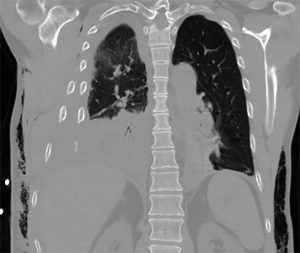

That was understandable. Custy had broken 8 of the 12 ribs on his right side in the fall. Five broke in two places, leaving them floating free of the chest wall. He’d also bruised and lacerated his right lung. That caused a “significant” air leak, and blood entered the cavity surrounding and lining the lung, said Peltz, who took on Custy’s case when he arrived at the ED.

Custy went to the hospital’s Surgical/Trauma Intensive Care Unit, where staff helped to manage his breathing and pain, which was considerable. For a week, Peltz and his team consulted with Custy and his family. They decided to wait in hopes of the ribs beginning to heal together, but his punctured lung slowly collapsed, cutting its capacity by 30 percent. He was at risk for pneumonia and “permanent, severe pulmonary disability,” Peltz said.